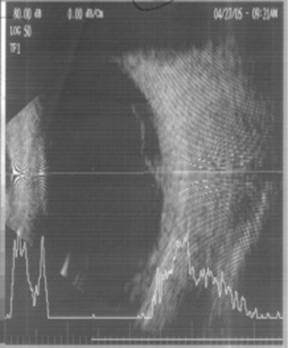

Ecografia oculara la OD deceleaza ecouri de intensitate subretiniana in treimea posterioara a vitrosului, in contact cu polul posterior, imobile cu miscarile globului ocular ; aspect coroidian ingrosat (fig.4 Aspectul ecografic la OS este cvasinormal.

Fig.4 OD -aspect ecografic preoperator